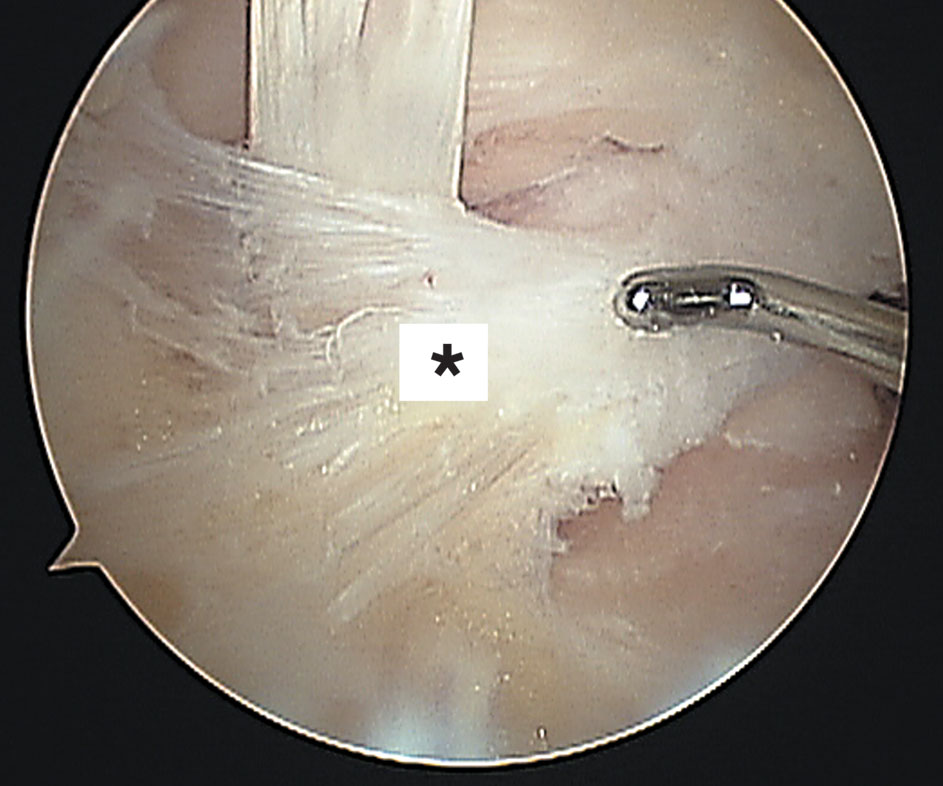

Si empezamos de atrás para adelante después de la piel y el tejido celular subcutáneo nos encontramos con fibras profundas de la fascia crural, que Rouviére y Canela llamaron ligamento fibulotalocalcáneo (Fig. 2).

Figura 2: Vista artroscópica del ligamento fibulotalocalcáneo